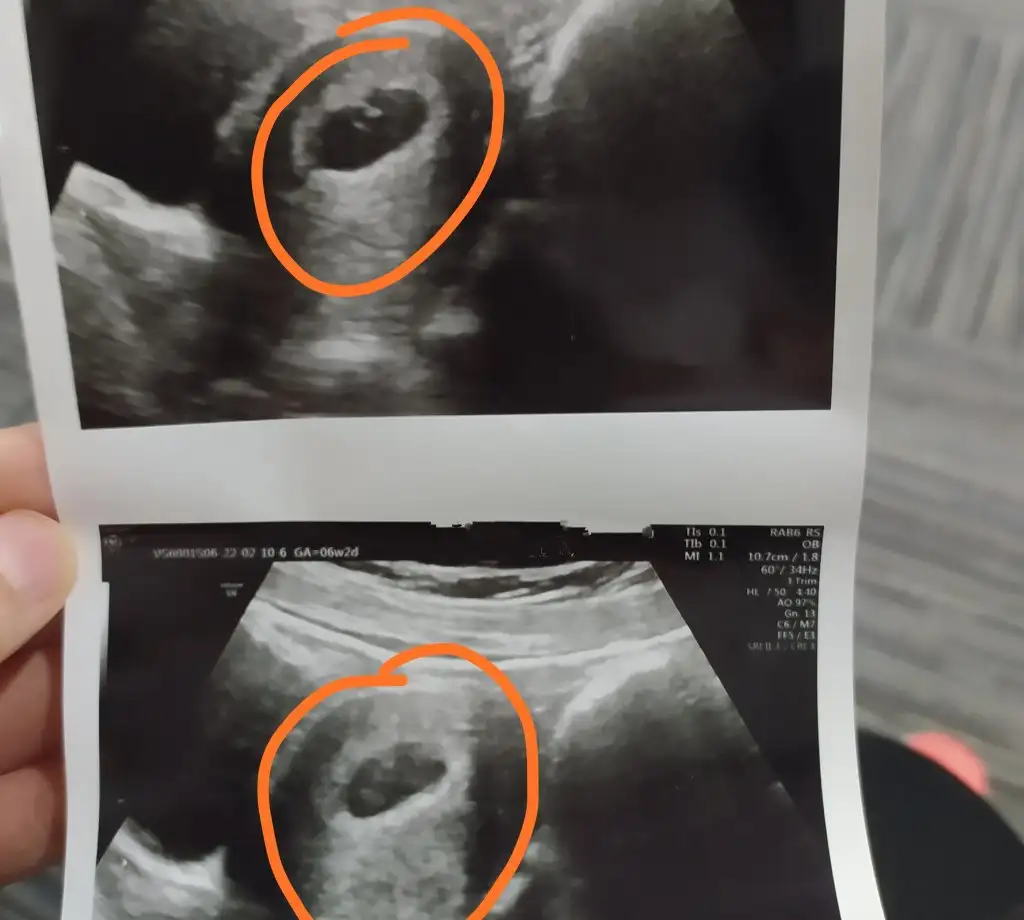

Eklentiler

• IMG_20220210_170258.webp

IMG_20220210_170258.webp

25,8 KB · Görüntüleme: 66

Erkege benziyor canım kesenin sağ tarafına yakın bebek inşallah kbryummy ilk baktığımda da bu şekilde yorumlamistim şükür dualarla beraber o güzel haberi aldı inşallah sende o güzel haberi duyarsın iki ay sonra 💙💙💙💙